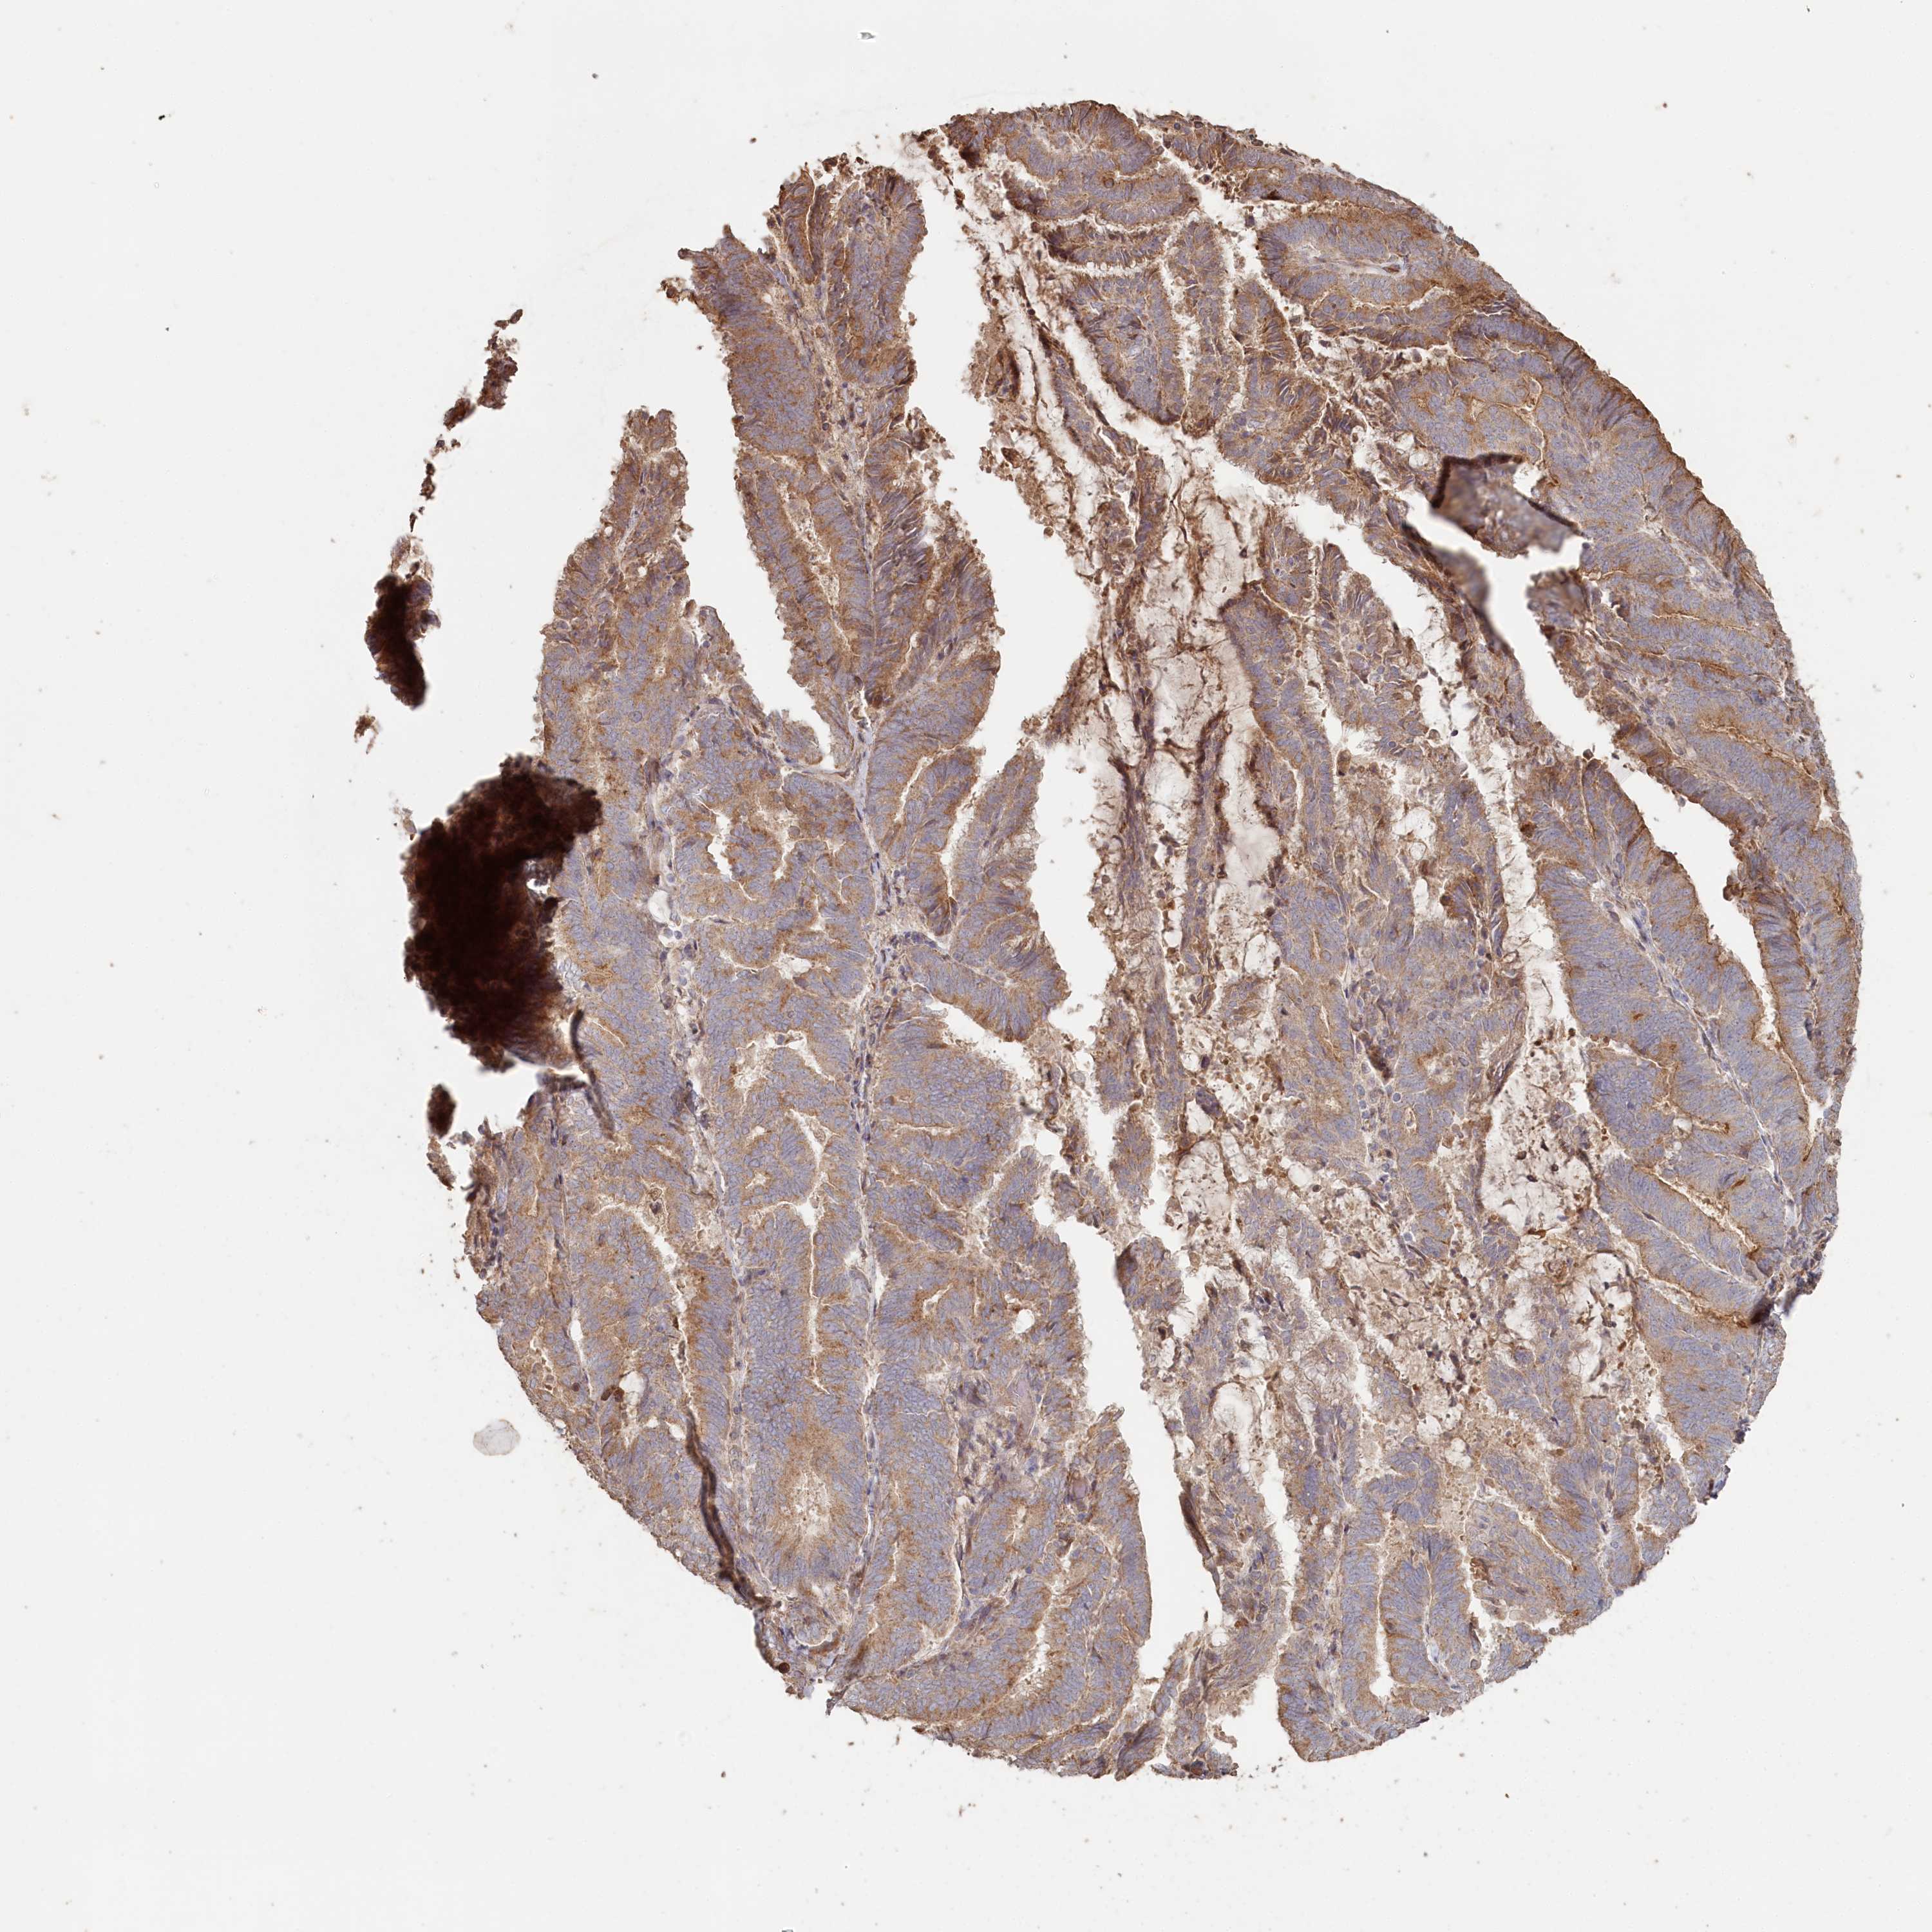

ENDOMETRIAL CANCER - Protein expressioni

A mouse-over function shows sample information and annotation data. Click on an image to view it in a full screen mode. Samples can be filtered based on level of antibody staining by selecting one or several of the following categories: high, medium, low and not detected. The assay and annotation is described here.

Note that samples used for immunohistochemistry by the Human Protein Atlas do not correspond to samples in the TCGA dataset.

Antibody stainingi

Antibody staining in the annotated cell types in the current human tissue is reported as not detected, low, medium, or high, based on conventional immunohistochemistry profiling in selected tissues. This score is based on the combination of the staining intensity and fraction of stained cells.

Each image is clickable and will lead to virtual microscopy that enables deeper exploration of all samples and also displays staining intensity scores, fraction scores and subcellular localization as well as patient and tissue information for each sample.

Antibody HPA038547

Antibody HPA038548

Staining

High

Medium

Low

Not detected

Intensity

Strong

Moderate

Weak

Negative

Quantity

>75%

75%-25%

<25%

None

Location

Nuclear

Cytoplasmic/membranous

Cytoplasmic/membranous,nuclear

Adenocarcinoma, NOS